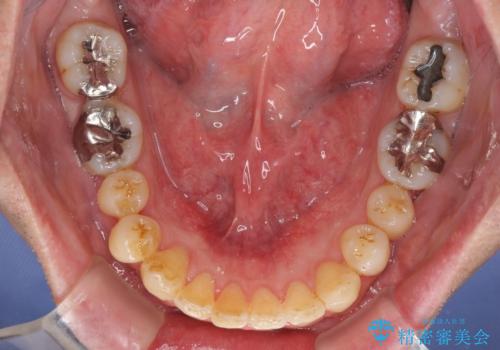

- 外に飛び出した側方の歯と、前歯のデコボコを気にして来院された患者様です。

IPR(歯と歯の間を削る)によってデコボコが解消するように設計し、インビザラインにより治療を行うこととしました。

治療途中で1年半以上通院されない時期があったため、後戻りが生じたことで治療期間が長くなってしまいました。

親知らずを抜去したことで、下顎のデコボコがきれいに解消されました。